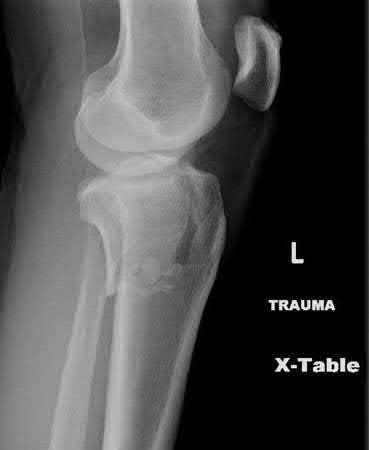

A 38-year-old male suffers the injury shown in Figure A. During operative fixation, free osteoarticular fragments are encountered and reconstruction of these pieces is attempted. Postoperatively, which of the following will have the most beneficial effect on the healing potential of the surviving chondrocytes within these reconstructed articular segments?

Figure A demonstrates a comminuted tibial plateau fracture with significant intra-articular involvement. Basic science evidence has demonstrated that post-operative gentle compressive loading may have a positive impact on articular cartilage healing; however, excessive shear loading may be detrimental.

Irrgang et al provide guidelines for rehabilitation following surgical management of articular cartilage lesions of the knee. They state that after articular cartilage repair, exercises to enhance muscle function must be done in a manner which minimizes shear loading of the joint surfaces in the area of the lesion. The authors also discuss the benefits of gentle compressive loading and motion of the joint, and its positive effects on chondrocyte nutrition.

Furthermore, they recommend a period of protected weight bearing as often being necessary, and that this should be followed by progressive loading of the joint.